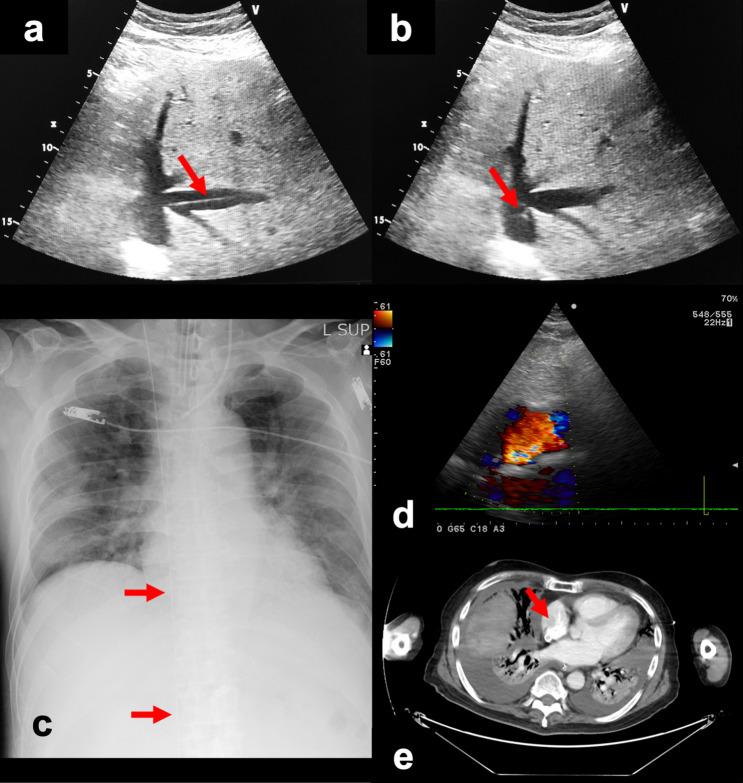

A case of successful bedside cannulation with a bicaval dual-lumen cannula guided by transthoracic echocardiography and mobile X-ray for veno-venous extracorporeal membrane oxygenation.